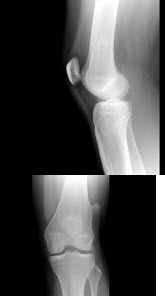

110、单项选择题

女,根据其正常膝关节影像图像,判断其最可能的年龄()

A.5岁左右

B.11岁左右

C.17岁左右

D.23岁左右

E.29岁左右